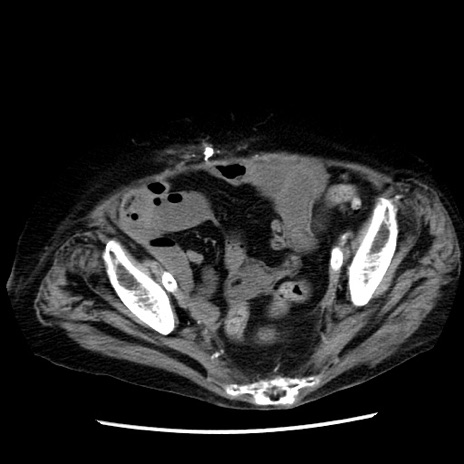

症例14(横断像)

【症例】 90歳代女性

【主訴】 腹痛・嘔吐

【現病歴】今朝から左側腹部痛を認めた。 経過観察していたが、嘔吐を認めたため来院。

【既往歴】 子宮癌術後

【身体所見】 意識清明、BP 127/54mmHg、P 98bpm Sp02 95%(RA)、BT 35.8°C、腹部平坦・軟腸ぜん動音聴取良好、右下腹部圧痛(+) 反跳痛なし

【データ】WBC 9800、CRP 0.46